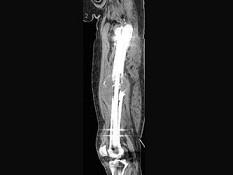

问题 男,18岁,右股骨肿瘤术后,出现大腿中段疼痛,夜间尤甚,结合CT图像,最可能的诊断是?(?)

选项 A.骨纤维肉瘤 B.尤文肉瘤 C.骨肉瘤 D.成骨性骨转移瘤 E.化脓性骨髓炎

答案 C